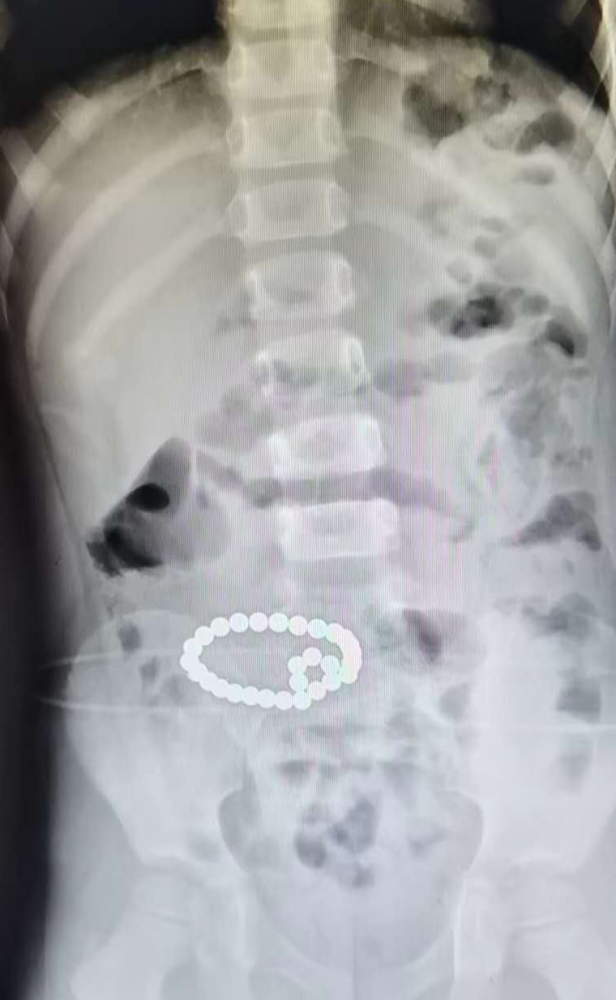

去年6月,一位医生发了一条朋友圈,配图瞬间炸锅了:这是一个6岁男孩的X光片,其中最惹人注意的就是肚子那块儿的“项链”。

但事实上,这根本就不是项链,而是29颗磁力珠连成了串!

到医院的时候,男孩已经腹痛了两天,家长以为是普通的肠炎,就给孩子吃益生菌助消化。在没有产生效果后,就跑到了医院。

接诊的医生一眼就看出了肠穿孔,要求立即做全麻手术。一个半小时后,才把29颗磁力珠从孩子体内取了出来。

2018年,青岛一个11岁男孩吞掉了21颗磁力珠,靠着磁力的互吸,也串在了一起: